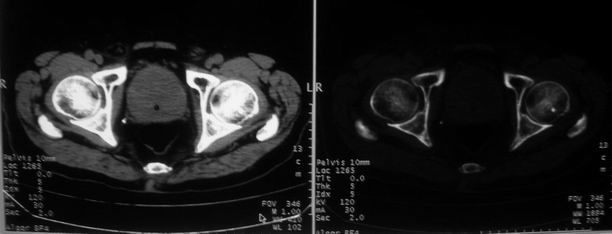

男,85岁,排尿困难。骶椎有问题吗?

前列腺明显增大,突入膀胱,各叶比例协调,密度均匀,精囊腺及精囊角正常;考虑良性增大。

这个病人排尿困难应该是前列腺增生造成的,ct对前列腺增生及前列腺癌诊断有一定限度,只能判断前列腺增大,建议还是做一个mr来鉴别一下增生或癌更好,因为增生多发生于中央带,癌多发生于周围带,而mr t2加权图像上中央带和周围带的信号有区别,因此诊断价值更高一些。

1)前列腺明显增大,突入膀胱,各叶比例协调,密度均匀,精囊腺及精囊角正常;考虑前列腺增生症并阻塞性膀胱炎。2)骶椎右侧类似囊状骨质密度减低区,边缘骨质硬化,其内为软组织密度影填塞,相邻之骶椎椎管受压变形;考虑为骶椎右侧囊肿或神经纤维瘤。

建议:行mri检查。